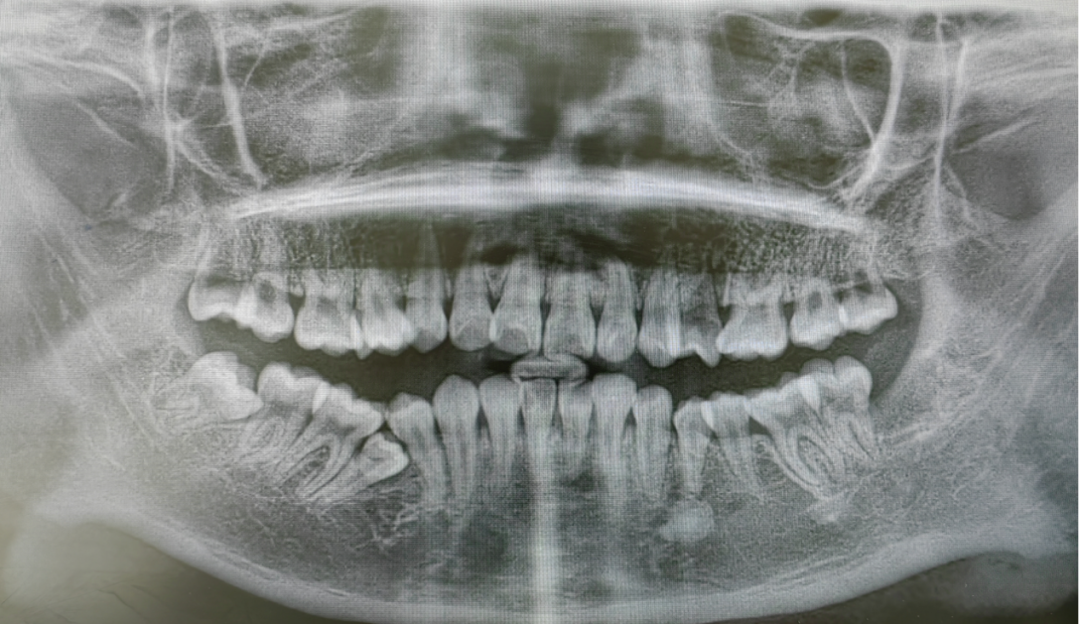

患儿术后X线片

短短15分钟,赵强就成功拔除了两颗患牙,治疗期间,口腔科医疗团队还贴心地准备了“解压小玩具”帮助小患者缓解紧张。治疗结束后,一旁的妈妈,激动地流下了泪水。妈妈表示:没想到这么快就拔完了两颗牙齿,更重要的是孩子很舒适放松,困扰她许久的孩子口腔治疗难题终于解决了。